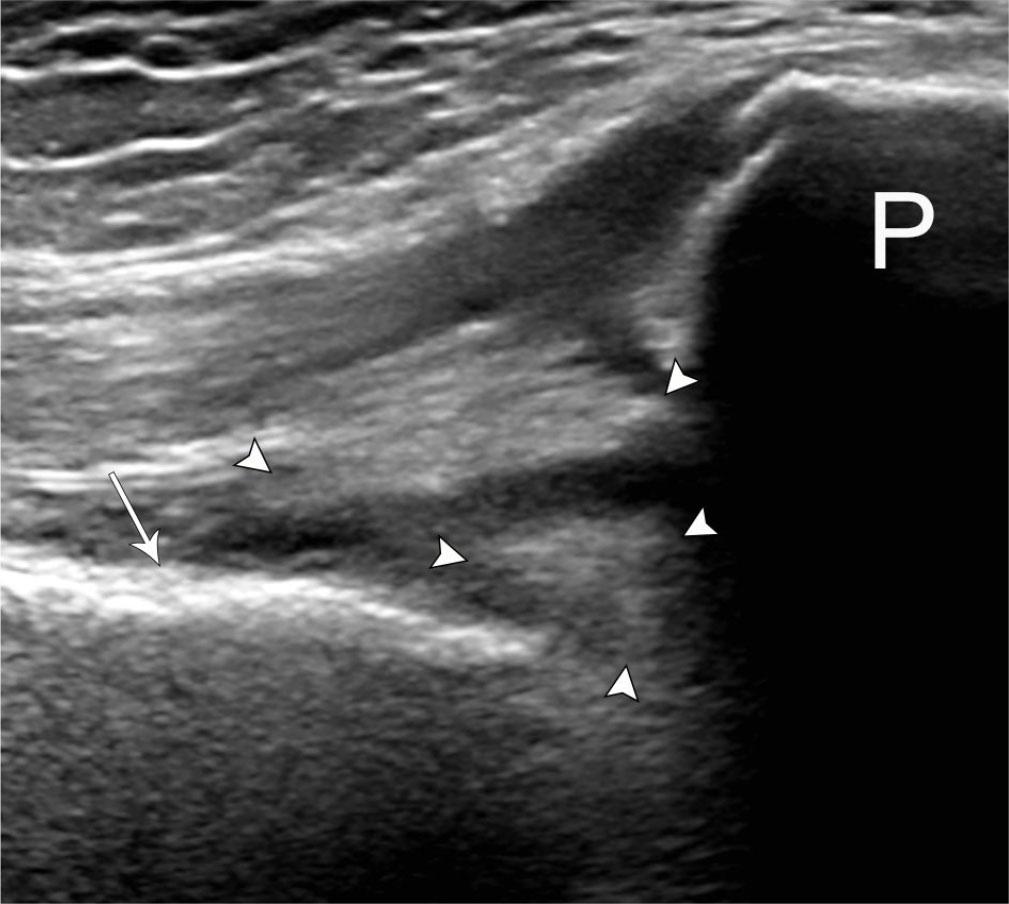

US allows the detection of intra-articular monosodium urate crystals, and one of the most specific diagnostic findings, the double contour sign, is a hyperechoic layer overlying the superficial margin of the anechoic hyaline articular cartilage atop the hyperechoic subchondral bone (Fig. 3)(19). This sign may be readily visualized at the distal femoral trochlear cartilage by maximally flexing the knee and placing the transducer superior to the patella. With a reported sensitivity and specificity up to 43.7% and 99%, respectively, this finding disappears when the serum uric acid level decreases below 6 mL/dL(7,20). As a result, it is best relied upon for diagnosing acute gout episodes and monitoring treatment response. It is important not to mistake the hyperechoic foci within the hyaline articular cartilage seen with calcium pyrophosphate deposition for gout(21).

Fig. 3.

76-year-old male with acute-onset left knee pain and history of gout. Transverse grayscale US image at the level of the femoral trochlea demonstrates smooth hyperechoic layer (black arrowheads) overlying the hypoechoic hyaline articular cartilage and paralleling the hyperechoic subchondral bone (white arrowheads), consistent with layering uric acid crystals